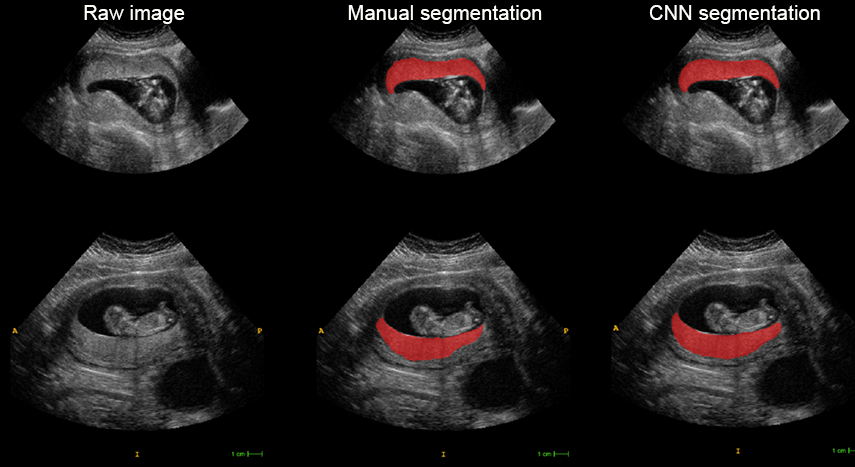

Vanderbilt University computer scientist and grant PI Ipek Oguz aims to expand a medical image analysis tool she developed, with researchers in the Perelman School of Medicine (PSOM) at the University of Pennsylvania, that tracks placental growth in relation to fetal growth and could better identify at-risk pregnancies. Currently, her innovative model requires a placental volume assessment that is impractical for clinical use. Nadav Schwartz, MD, an associate professor of Obstetrics and Gynecology at PSOM, is co-PI on the grant.

The new augmented version of the model will include later gestational ages and expand the toolkit to include measures of placental shape and blood vessels. “We’ll have a volume, shape and surface analysis of the baby side and the mother side of the placenta,” Oguz said.